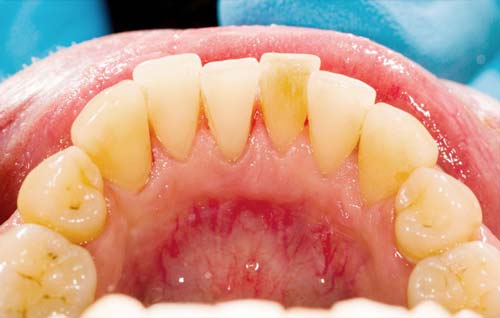

تصویر همین دندانها پس از جرمگیری در پایین آمده است:

به محض این که پلاک به جرم سخت تبدیل شود، تنها دندانپزشک میتواند آن را تمیز کند. دندانپزشک با استفاده از ابزارهای فلزی مخصوص یا ابزار اولتراسونیک دندانپزشکی، جرمها را پاک میکند.

اگر دوباره به تصاویر بالا نگاه کنید، میبینید که لثه های بیمار دچار پسروی شده اند که علت آن تحریک و التهاب ناشی از رسوب و جرمهای موجود در سطح دندان است.